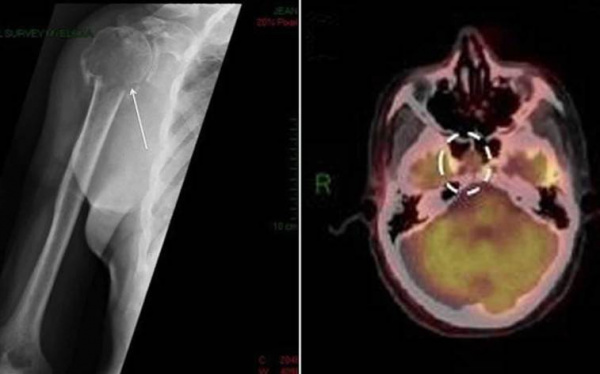

- Рентгенодиагностика. При костных болях назначается рентгенография грудной клетки, позвоночника и конечностей, с помощью которой определяются объемные новообразования. Для точной визуализации опухолей и определения степени распространенности процесса проводится КТ пораженной области тела. Методика ПЭТ-КТ показана для диагностики генерализованной плазмоцитомы.